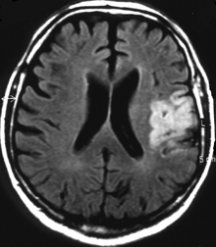

In a small pilot study of people with stroke in Germany, 20 patients treated with EPO within 7 hours of stroke later had fewer physical, speech, and memory problems and needed less day-to-day assistance than did 20 who didn’t get the hormone. People treated with EPO also tended to have smaller areas of damaged brain tissue, as measured by brain scans a month after their stroke.

People who have had the most-severe strokes seem to benefit most from treatment with EPO, reports Hannelore Ehrenreich of the Max-Planck Institute for Experimental Medicine in Göttingen, Germany. She and her colleagues published their findings in the August Molecular Medicine. The German team is now developing a trial of about 500 patients at several medical centers.